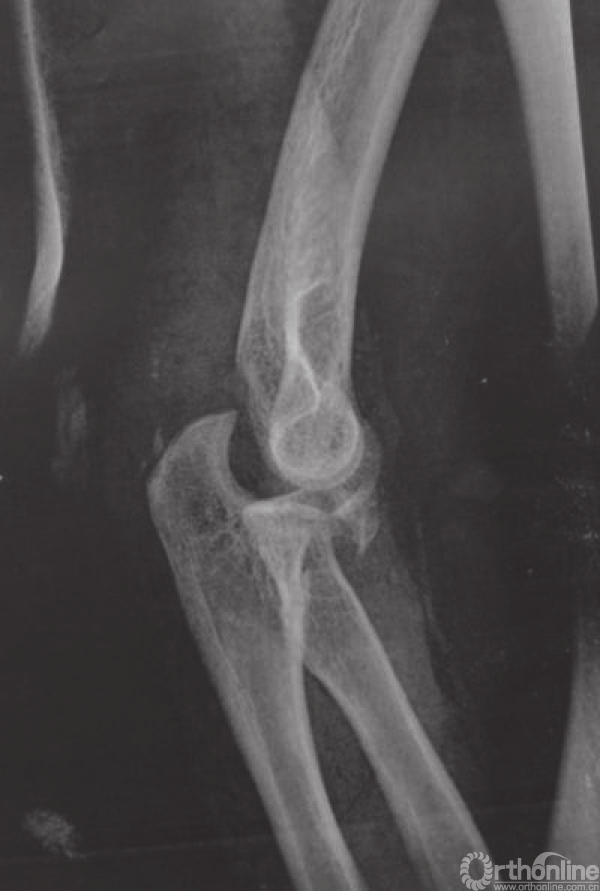

图2患者,男,35岁,左肘关节三联征,冠状突骨折O’Driscoll分型为尖部骨折第二亚型,桡骨头前侧剥脱约10%,Mason分型Ⅱ型

a.术前侧位X线片;